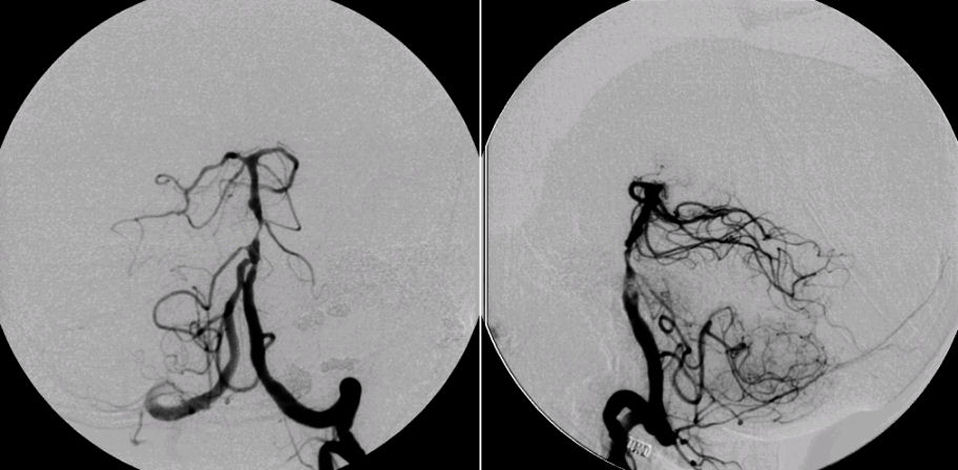

척추뇌바닥동맥 협착(Vertebrobasilar artery stenosis)

• 치료: 내과적 치료

• 반복되는 허혈증상 → 스텐트 설치술 고려